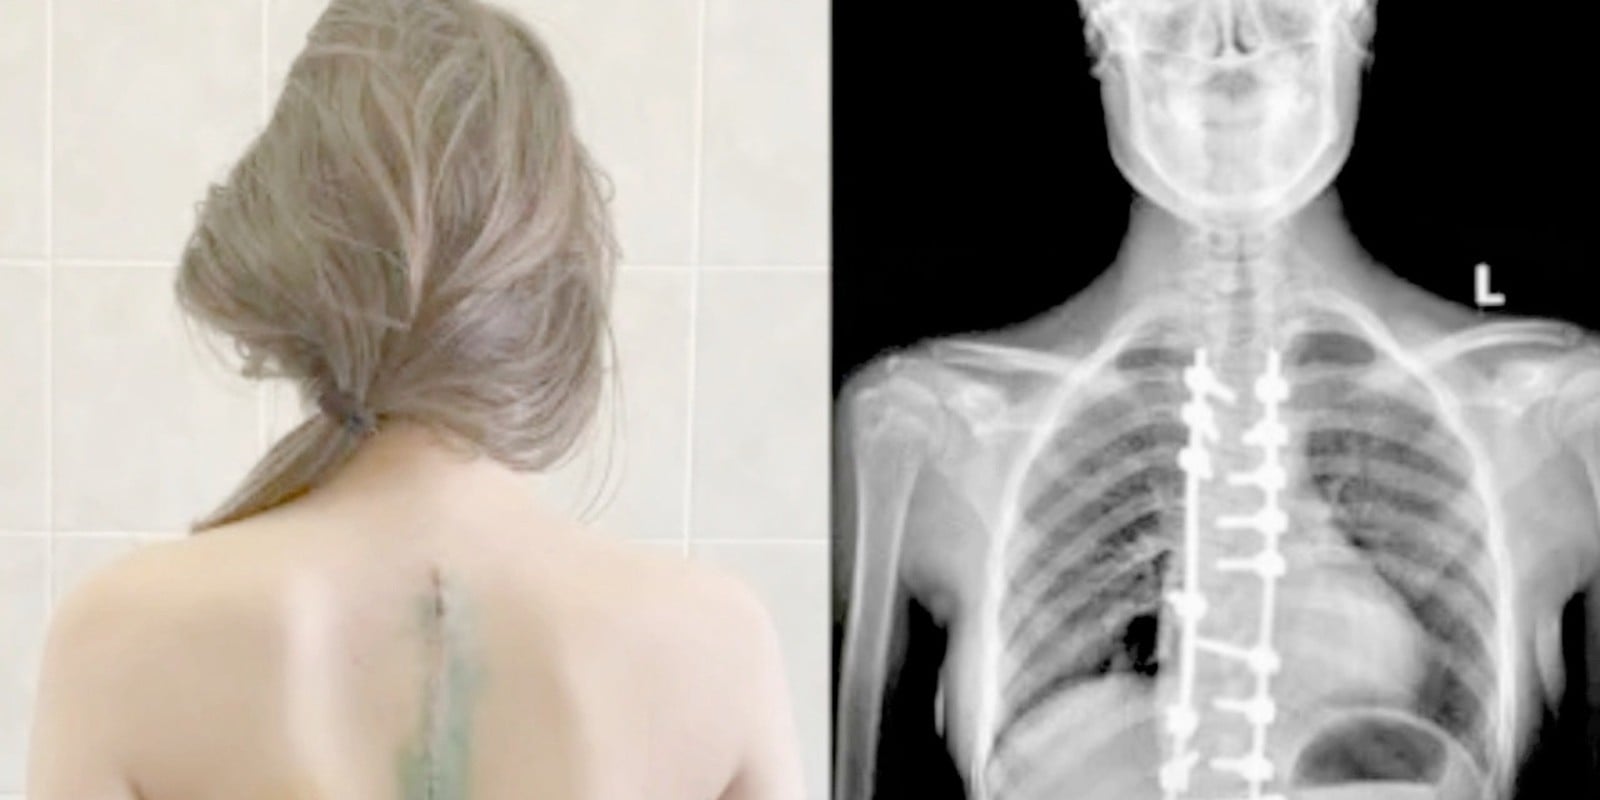

Он повесил снимок на экран. Позвоночник моей дочери. И вдоль него — россыпь белых точек. Много. Как будто кто-то рассыпал бисер внутри маленького тела.

— У вашей дочери нейробластома. Четвёртая стадия. Метастазы в костную ткань позвоночника, рёбер и, вероятно, таза. Нам нужна срочная биопсия и полное обследование, но по снимку… Денис, это запущено. Сильно запущено.

— Нейробластома. Четвёртая стадия. Метастазы по всему позвоночнику. Она болеет минимум с лета. Ты знала, что у неё болит спина. Знала — и не повела к врачу.

Я сидел и смотрел на неё. Не мог вдохнуть. Как будто воздух стал твёрдым и не помещался в лёгкие. Она протянула снимок — чистый позвоночник, без единой белой точки, без единой горошины бисера — и мне пришлось схватиться за стол, потому что комната поехала вбок.